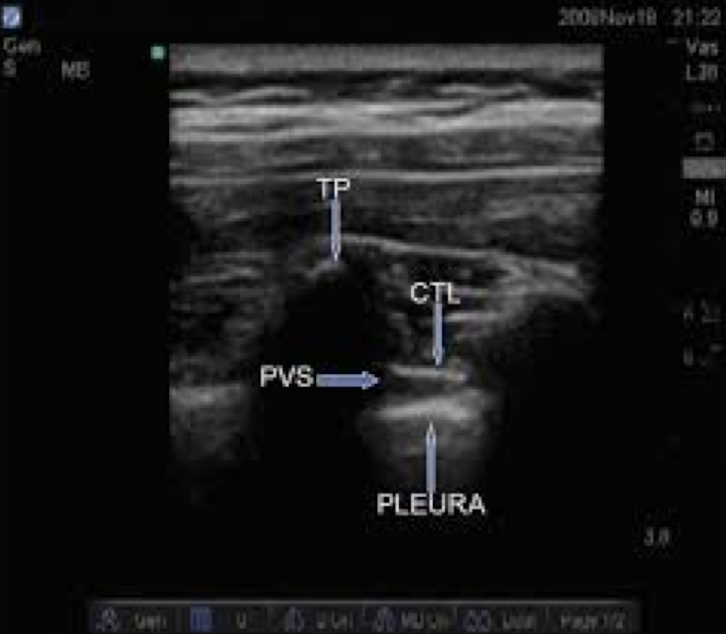

10

Q

name this block and structures

A

parasaggital in plane approach to PVB

transverse process

costotransverse ligament

paravertebral space

pleura

goal is depression of the pleura, shimmer may be seen

How well did you know this?